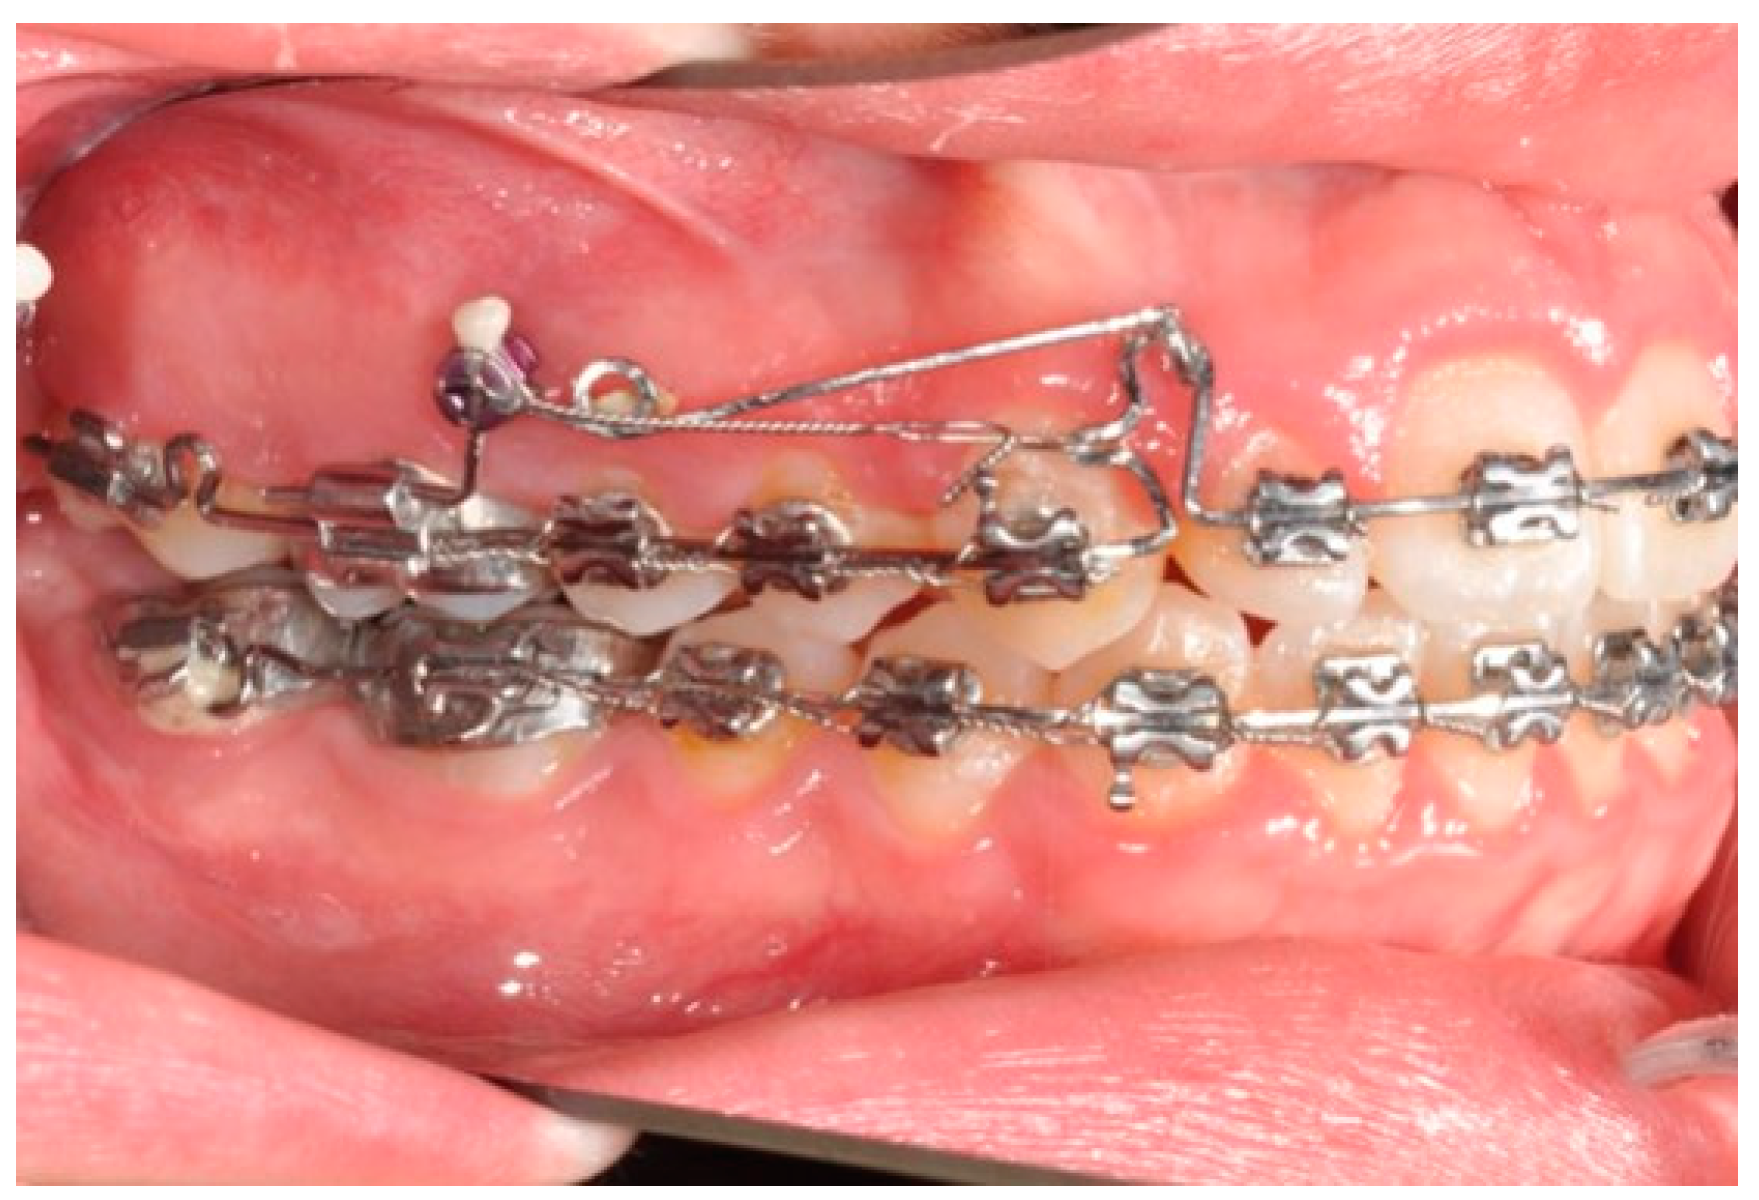

The helical bulbous loop produces space distally to the upper first molars. An open coil is added between the second bicuspid and the first molar in order to move to the distal second and first molar at the same time (Figure 4 and Figure 5). Eventually, an elastic module is placed between the hooks on the second molars and the first molars in order to finish the combined distalization of the upper first molars.

Figure 4. Molar and premolar distalization strategy.

Figure 6. Molar and premolar distalization strategy: Hooks are placed between the laterals and the cuspids. Third-class elastics (1/4” 6 0z) are placed from the tads to the hooks.